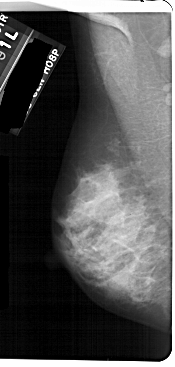

A_1736_1.LEFT_MLO

LEFT_MLO LINES 5491 PIXELS_PER_LINE 2611 BITS_PER_PIXEL 12 RESOLUTION 43.5 NON_OVERLAY